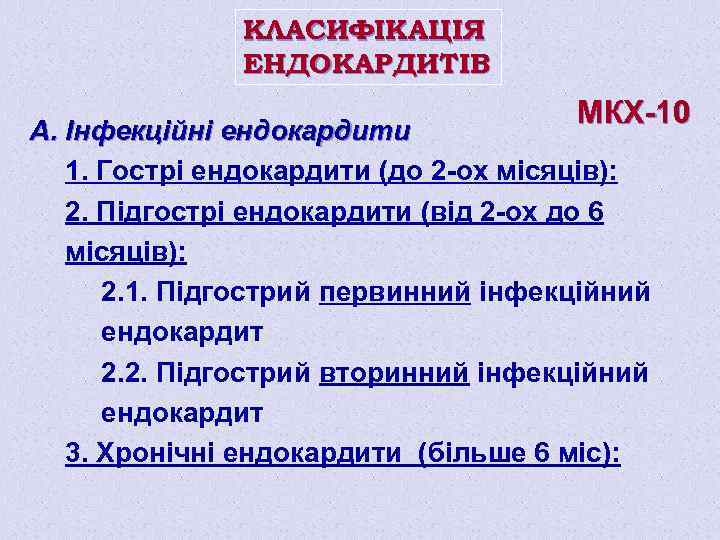

КЛАСИФІКАЦІЯ ЕНДОКАРДИТІВ МКХ-10 А. Інфекційні ендокардити 1. Гострі ендокардити (до 2 -ох місяців): 2. Підгострі ендокардити (від 2 -ох до 6 місяців): 2. 1. Підгострий первинний інфекційний ендокардит 2. 2. Підгострий вторинний інфекційний ендокардит 3. Хронічні ендокардити (більше 6 міс):